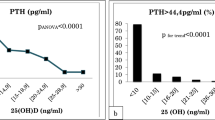

Relationship between 25(OH)D and PTH, and the threshold for vitamin D status

To illustrate the relationship between PTH and 25(OH)D concentrations, we first stratified the 25(OH)D concentrations in 13 groups at an increment interval of 10 nmol/L, i.e., the first group was 25(OH)D < 10 nmol/L and the final group was 25(OH)D ≥ 120 nmol/L (Fig. 2A). As shown in Fig. 2A, there was a nonlinear negative correlation between serum 25(OH)D and PTH. Considering the complexity of the relationship, we adopted LOESS method to fit a smooth curve (Fig. 2B). Both the column chart and the LOESS curve visually suggested that there might be two 25(OH)D inflection points. Using segmented regression, it was suggested that PTH reached its plateau (decreased slightly) when 25(OH)D was 55 nmol/L or more, while PTH rose steeply when 25(OH)D was less than 22 nmol/L. Therefore, we defined vitamin D status as: sufficient (≥ 55 nmol/L), insufficient (22–55 nmol/L), and deficient (< 22 nmol/L). Multivariate linear regression coefficients of 25(OH)D in subjects with varied 25(OH)D concentrations are listed in Table 2, and weakened coefficient was observed in subjects with 25(OH)D sufficient.

Serum PTH concentration according to 25(OH)D status (n = 64,979). A Histograms between 13 groups of different 25(OH)D concentrations and PTH concentrations. B Locally weighted regression smoothing (LOESS) curves between concentrations of 25(OH)D and PTH. Red triangles: cutoff values determined by segmented regression (22 nmol/L, 55 nmol/L)

By evaluating the relationship between 25(OH)D and PTH, we calculated a 25(OH)D threshold of ≥ 55 nmol/L for vitamin D sufficiency and a 25(OH)D threshold of < 22 nmol/L for vitamin D deficiency. Although currently, there has been no universally accepted 25(OH)D threshold for vitamin D status, the estimated 25(OH)D cutoff values in this study were close to those recommended by the IOM guidelines [29].